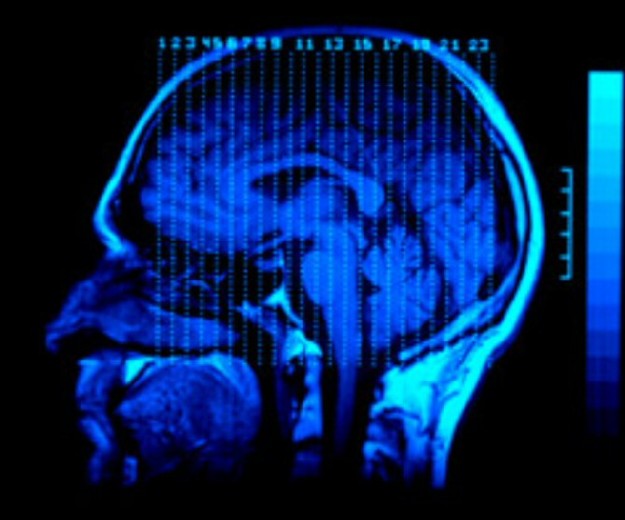

¿Haber sufrido un traumatismo craneoencefálico aumenta el riesgo de cometer un crimen violento?

Sin embargo, un resultado de este mismo estudio, que sin duda generará controversias, sugiere que en las personas que han experimentado traumatismos craneoencefálicos sí existe un riesgo mayor de cometer posteriormente un delito violento. La polémica está servida.

El equipo de Seena Fazel de la Universidad de Oxford en el Reino Unido, y colegas del Instituto Karolinska en Suecia, y del Servicio Sueco de Prisiones y Libertad Condicional, identificaron a todas las personas con epilepsia y traumatismo craneoencefálico registradas en Suecia entre 1973 y 2009, y compararon cada caso con diez personas de la población general que no padecieron estos problemas cerebrales.

Los investigadores cotejaron esta información con la de las condenas judiciales por delitos violentos. Para ello se valieron de los números de identificación personal de los residentes suecos en el Registro Nacional.

Usando estos métodos, los autores encontraron en un primer momento que el 4,2 por ciento de las personas con epilepsia había sufrido al menos una condena por actos violentos después de su diagnóstico, en comparación con el 2,5 por ciento de la población general. Sin embargo, después de evaluar otros factores, incluyendo la situación familiar (en esencia, comparar a las personas epilépticas con sus hermanos o hermanas sin la enfermedad), esa aparente asociación entre padecer epilepsia y ser condenado por un delito violento desapareció.![[Img #6561]](upload/img/periodico/img_6561.jpg)

En cambio, los autores del estudio sí encontraron en las personas aquejadas de traumatismo craneoencefálico una asociación entre haber sufrido esta lesión y perpetrar un delito violento. La asociación se mantuvo incluso después de tener en cuenta la influencia del consumo de drogas, y de comparar a las víctimas de traumatismo craneoencefálico con sus hermanos o hermanas sin lesión.